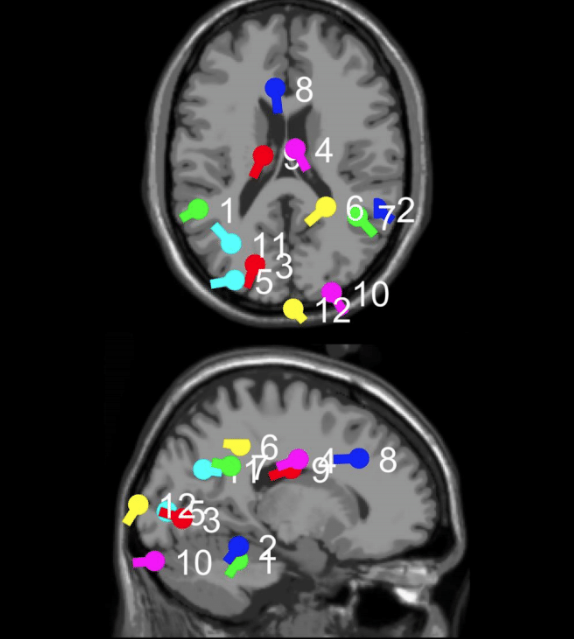

For the analysis portion of the QEEG, Whitney works with Dr. Rob Coben at Integrate Brain Health in Fayetteville. Dr. Coben is an expert in a highly effective, specific version of coherence training that he originated called “4-channel multivariate coherence training.” You can learn more about Dr. Coben and his work on the Integrate Brain Health website. His site includes a wide variety of videos, research, and other resources.